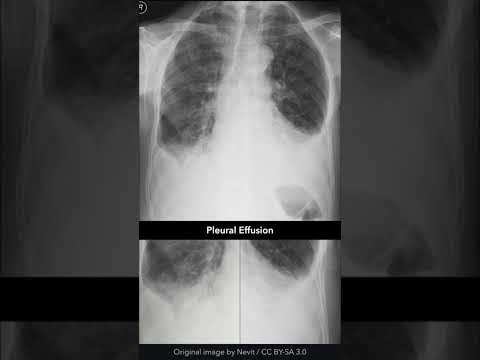

Chest X-ray Normal vs Pleural Effusion #radiography #radiographerusn #xray #shorts

Pleural Effusion Chest X-ray #shorts